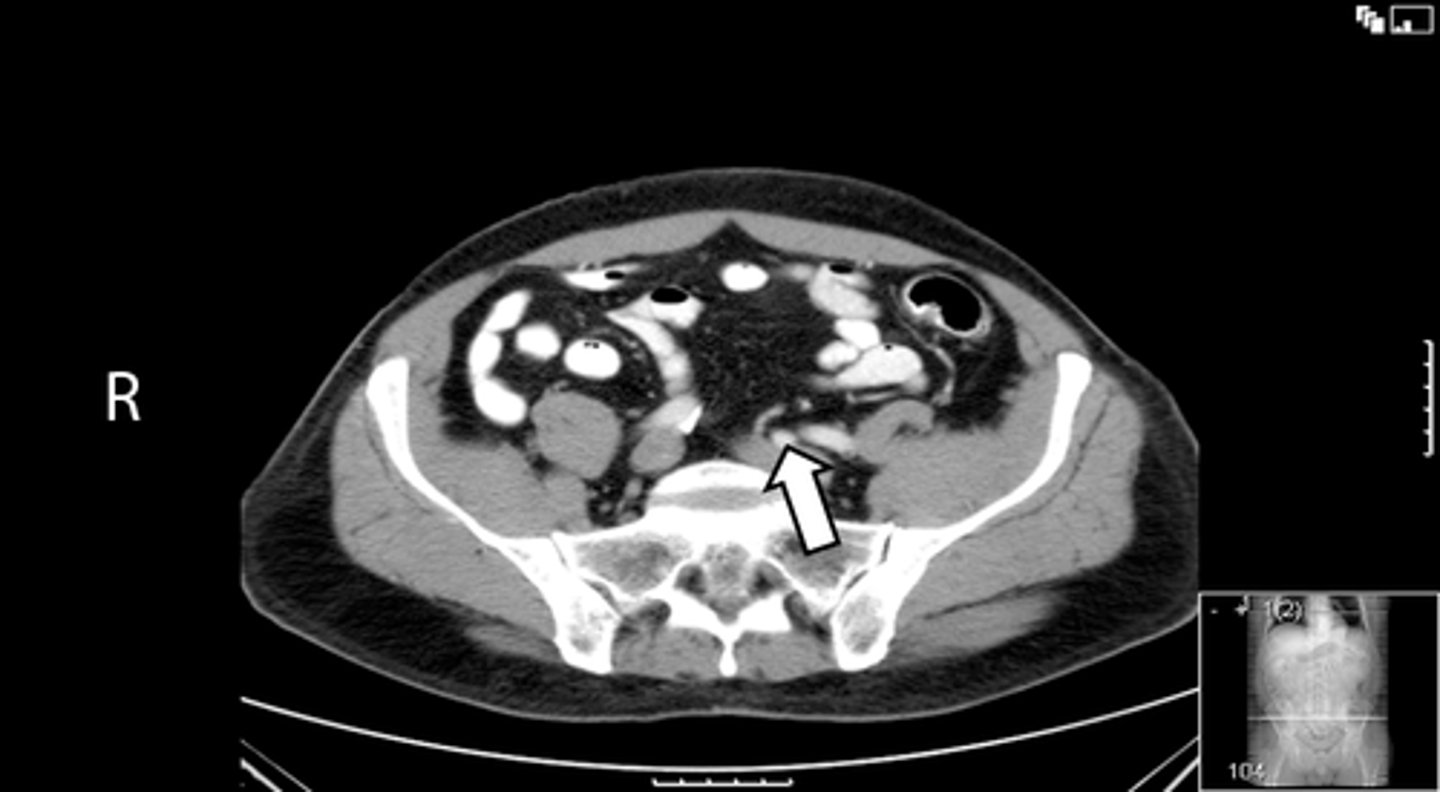

Axial bony pelvis CT

What is the image?

32

L ilium

What is indicated in the image?

<p>What is indicated in the image?</p>

33

New cards

L sacroiliac joint

34

R ilium

35

R sacroiliac joint

36

Sacrum